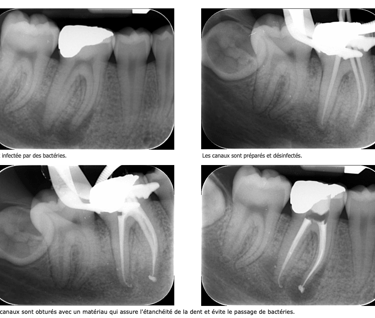

En présence d'une inflammation irréversible ou d'une infection , le chirurgien dentiste est amené à réaliser un traitement endodontique qui permet de supprimer l’ensemble des tissus infectés se trouvant dans les canaux radiculaires.

Au cours de ce traitement, l’ensemble des canaux sont nettoyés, désinfectés et enfin obturés afin d’éviter toute réinfection.

Ce traitement est réalisé sous anesthésie locale, comme n’importe quel soin. Le traitement endodontique permettra de désinfecter l’ensemble des canaux.